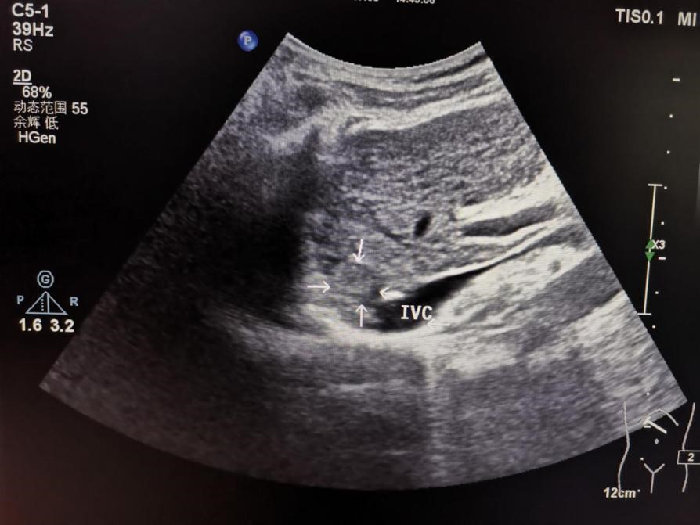

箭头所指病灶紧邻膈肌及下腔静脉

7月8日下午进行手术,超声诊断科主任医师肖迎聪、骆会婷指导,超声造影再次锁定病灶,采用基础麻醉加局麻,王涛徒手进针,当针刺入肝脏时仿佛空气都凝固了,针尖经过肝静脉时用特殊手法顺利避开,缓慢稳定的刺入病灶内,此时消融针已进入肝脏10cm。固定消融针后,再次进入PTC针,由于病灶较小,操作空间更小,第二根针的进入更难,王涛精准操作,成功的将第二针布到肿瘤边缘与下腔静脉的微小间隙当中。开始消融,大家的眼睛都紧盯膈肌与下腔静脉,当肿瘤瞬间变化时及时停止消融,同时PTC针推入2ml聚桂醇立刻拔针,术后即刻超声造影评估消融范围,显示无灌注区完全覆盖肿瘤,下腔静脉、膈肌以及肝静脉未见异常,手术成功。

超声实时引导下消融针精准到达病灶